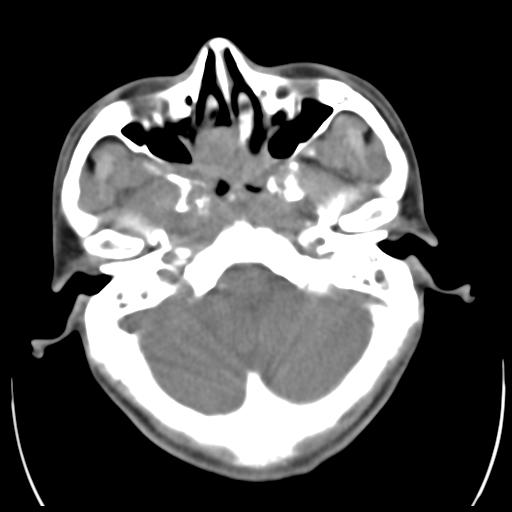

35m 鼻子时不时流血,头及右侧面部痛,颈部淋巴结未见明显大

骨窗

蝶窦,后组筛窦及鼻咽部团块状软组织影,骨壁破坏,病变较广泛。考虑恶性肉芽肿。建议活检。

颅底骨质明显破坏 支持鼻咽癌 但病灶的边缘毛糙 不能除外炎性

考虑中线肉芽肿(鼻硬结病),次之tb或真菌感染性肉芽肿,病变形态不像肿瘤,建议增强及活检。

颅底骨质不是那种溶骨性的破坏吗?